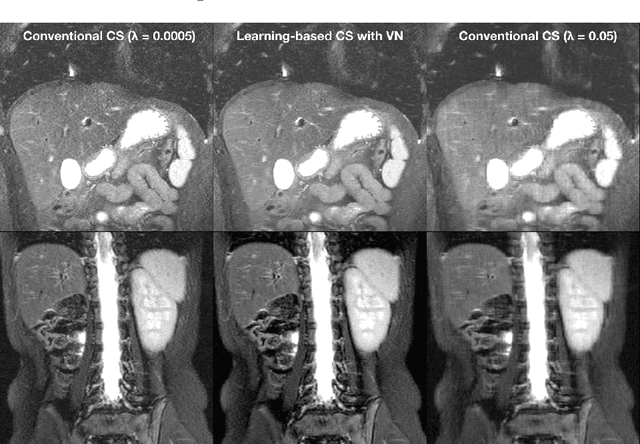

Abstract:Compressed sensing in MRI enables high subsampling factors while maintaining diagnostic image quality. This technique enables shortened scan durations and/or improved image resolution. Further, compressed sensing can increase the diagnostic information and value from each scan performed. Overall, compressed sensing has significant clinical impact in improving the diagnostic quality and patient experience for imaging exams. However, a number of challenges exist when moving compressed sensing from research to the clinic. These challenges include hand-crafted image priors, sensitive tuning parameters, and long reconstruction times. Data-driven learning provides a solution to address these challenges. As a result, compressed sensing can have greater clinical impact. In this tutorial, we will review the compressed sensing formulation and outline steps needed to transform this formulation to a deep learning framework. Supplementary open source code in python will be used to demonstrate this approach with open databases. Further, we will discuss considerations in applying data-driven compressed sensing in the clinical setting.